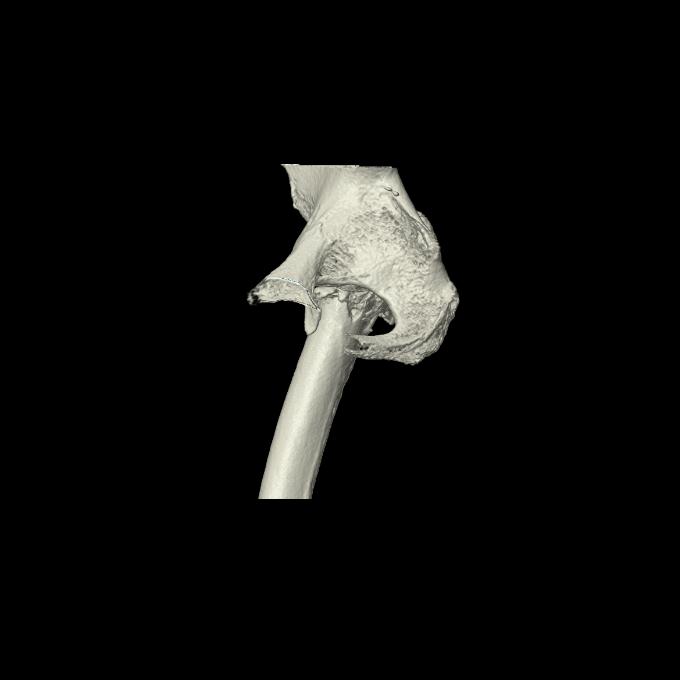

110286 2/17 股関節 2R 74歳女性 右人工骨頭